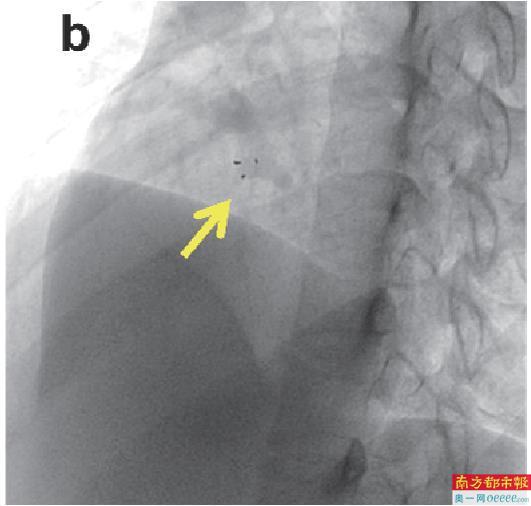

(a)可降解封堵器植入后超声影像。

(c)传统金属封堵器植入后X线影像。箭头所示为封堵器,在X线影像上可降解封堵器几乎不可见。